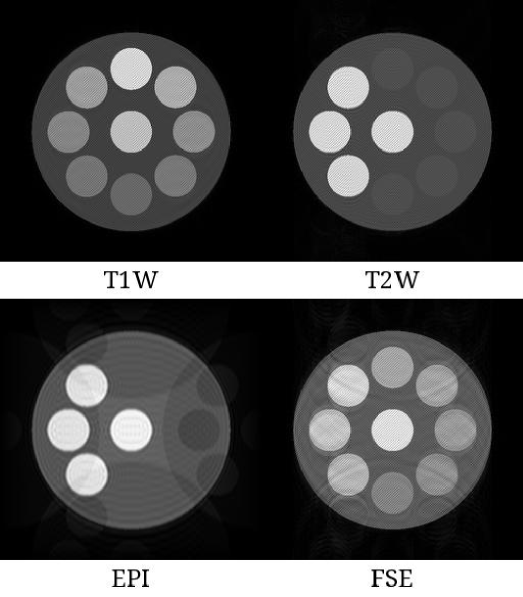

Refer to caption

Figure 5: Reconstructed images using the circles phantom. T1W, T2W, EPI and FSE sequences were used for the simulations. Each circle has a unique pair of T1T_{1} and T2T_{2} values. The images using EPI and FSE sequences included artifacts since no artifact elimination methods were used. Abbreviations: T1W, T1-weighted, T2W, T2-weighted, EPI, echo-planar imaging, FSE, fast spin echo.